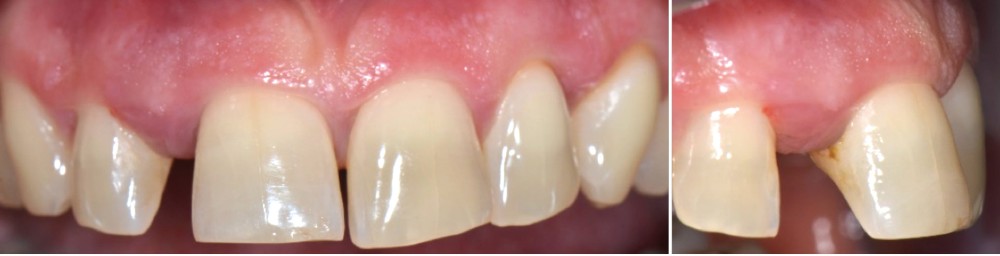

Formes cliniques

La MDP est dépendante de l’axe des forces appliquées à la dent. Ces forces peuvent ainsi conduire à des déplacements horizontaux, des versions (basculement par rotation) et/ou des égressions/extrusions (déplacement vertical seul, souvent retrouvé lors de la perte de dent antagoniste).

Des combinaisons de mouvements sont le plus souvent retrouvées, notamment lors de la perte du calage postérieur : déplacement horizontal et vertical, migration « en éventail ».